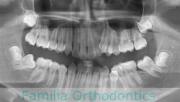

でこぼこを治したいということで来院されました。上下左右から親知らずも第一小臼歯も抜歯が必要で、歯科矯正アンカースクリューを併用して大臼歯を後ろに引っ張りながらの治療でした。3年弱、35回程度の通院が必要でした。

叢生が著しく、後戻りのリスクがあります。またアンカースクリューが必須のため、もしもスクリューが安定しないと、治療が難しく長くなってしまう恐れがありましたが、幸い脱落は見られませんでした。